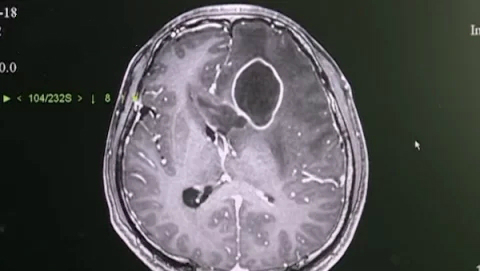

近日广东揭阳36岁的小周,最近这半年一直头疼,备受折磨,前段时间因为痛得越来越厉害,而且有点发烧,于是来到了南方医科大学中西医结合医院神经外科就诊。检查后才发现脑里面竟然有5公分大的脓肿,造成周围大范围的水肿,周围的脑组织,包括脑室系统都明显受压了。

小周的脑部为什么会有这么大一个脓肿的呢?在大家都觉得这个肯定是一个怪病的时候,陈主任详细地询问小周病史和日常生活的情况,得知小周特别挤痘痘和粉刺,“这个病人有一个不太好的习惯,每次有粉刺,他就会用牙签把粉刺戳破,这个不好的习惯,可能导致细菌入脑,引起脑脓肿”。